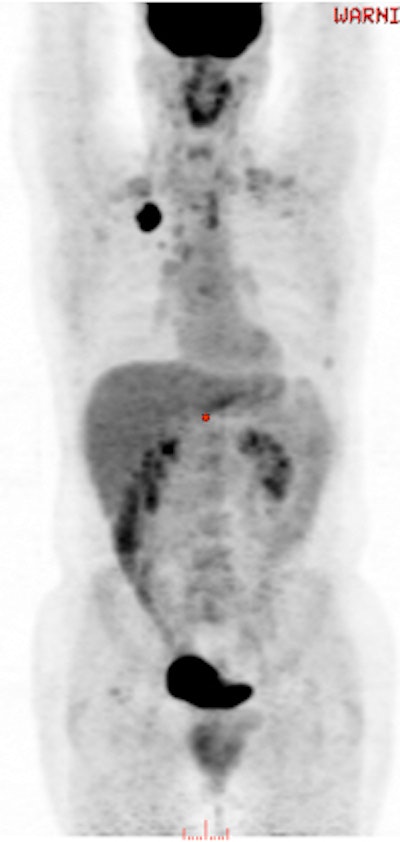

A 49-year-old male with non-small cell lung cancer received an FDG-PET scan three hours and 45 minutes after a treadmill stress test. The image reveals no conspicuous muscle uptake. SUVmax was 1.2 and SUVmean was 0.7. Image courtesy of Dr. Ashima Lyall.

The analysis found only minor, insignificant differences between assessments among the three groups. The only noteworthy exception was SUVmax in the quadriceps muscle in the first group of patients (SUVmax 1.41 ± 0.41, compared with 1.21 ± 0.48 and 1.36 ± 0.22 in the second and third groups, respectively). Image quality and visual assessment of other muscles were deemed similar.